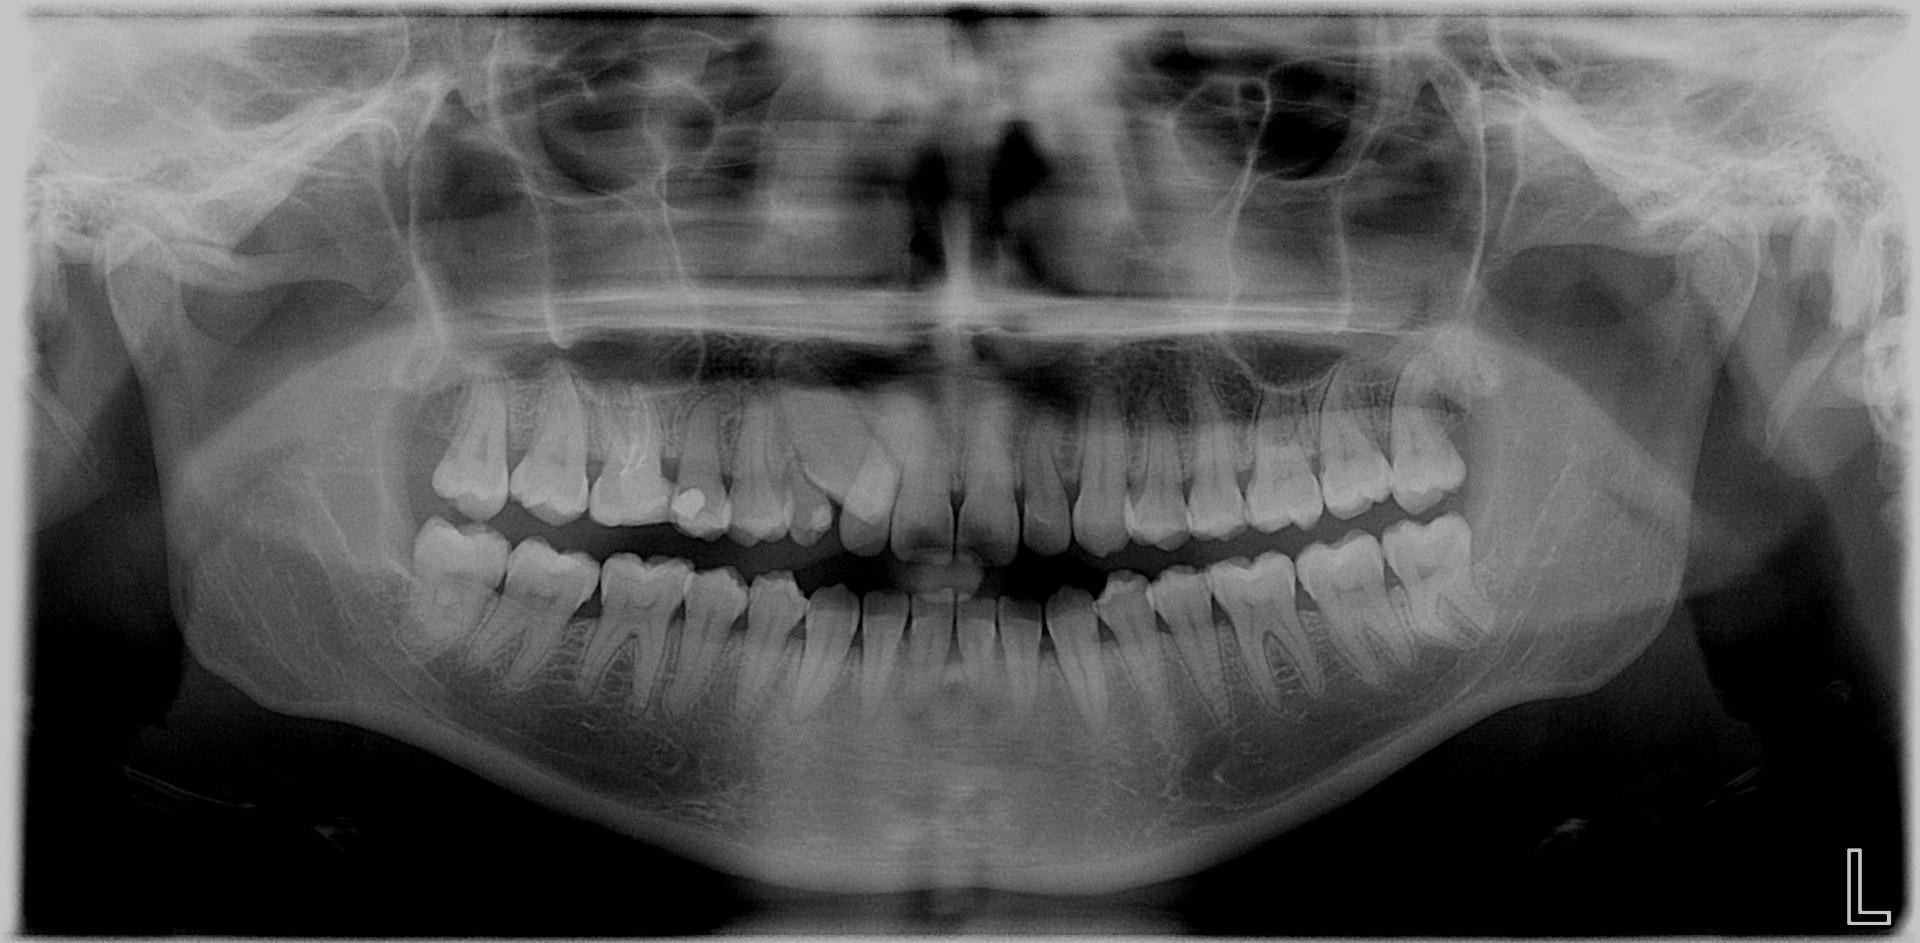

L’extraction des dents de sagesse consiste à enlever les troisièmes molaires du haut et/ou du bas. Chez l’enfant ou l’adolescent, ces dents n’ont pas terminé leur développement et sont appelés germes (l’intervention est appelée « germectomie »).

Ces dents doivent être extraites parce qu’elles sont en mauvaise position et sont à l’origine de douleurs et d’inflammation ou parce qu’elles risquent de perturber le bon alignement des dents chez l’enfant ou l’adolescent (l’indication est souvent portée par l’orthodontiste) .